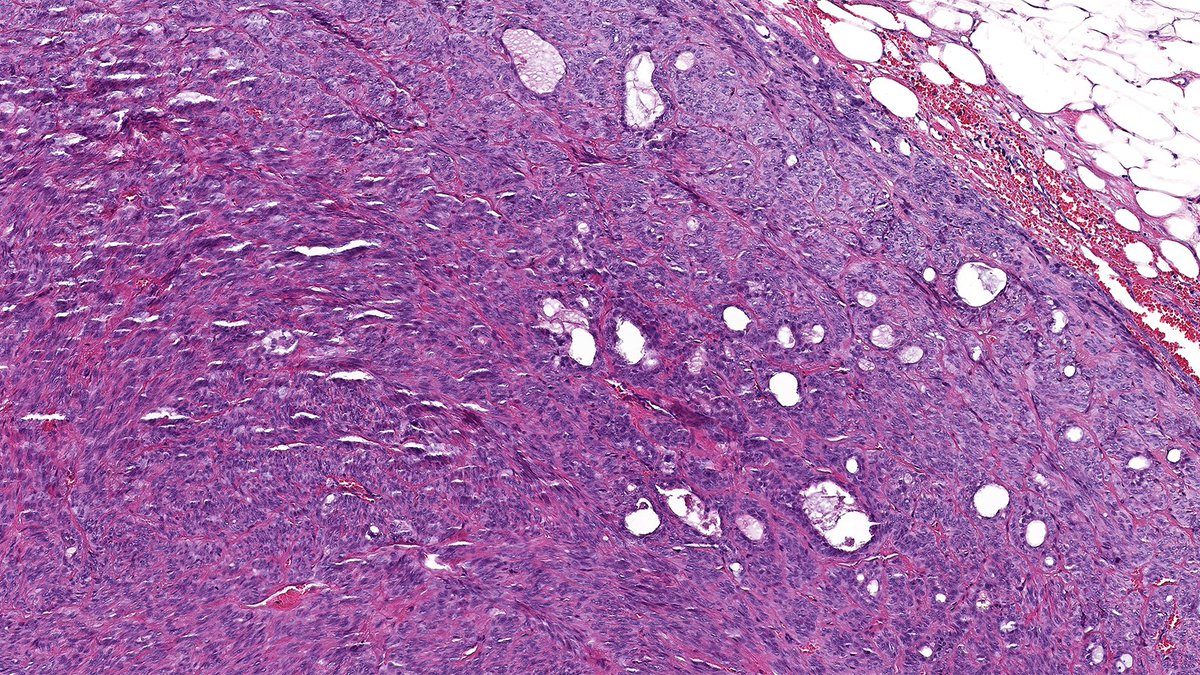

No doubt—you all crushed it! 💯 The answer: B-cell lymphoma. This one’s a marginal zone lymphoma of the breast—rare, and a great mimicker of lobular carcinoma. Hope this was a helpful review of the lobular carcinoma differential! #PathX #PathTwitter #breastpath #PathQuiz

Raza Hoda MD (@razahoda) 's Twitter Profile Photo